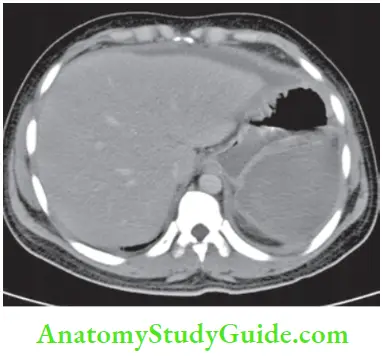

Most of these injuries are diagnosed by CT scan today (CT classification is given).

- CT scan is more reliable. It should be used in cases of doubtful diagnosis and stable patients.1 It also rules out hollow viscus perforation, pancreatic injuries, etc.